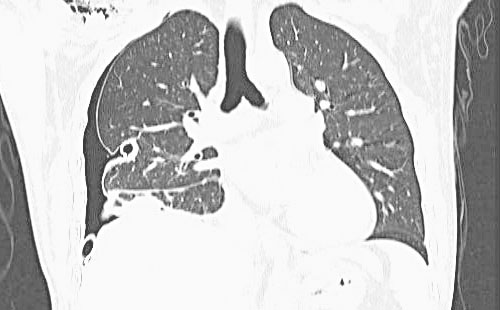

1)胸腹部增强CT:双侧胸腔积液伴两肺膨胀不全,右侧为著。经皮胆道镜碎石取石术后改变,胆管外引流管在位(图5)。

图5 腹部CT:胆管外引流管在位;胸部CT:右侧大量胸腔积液伴右肺不张